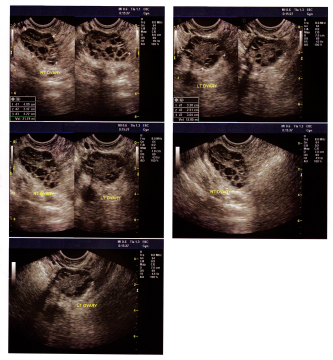

ДИАГНОСТИКА

Диагноз ставится на основании жалоб,анамнеза ,осмотра гинеколога и инструментальных исследований.УЗИ органов малого таза-самый распространенный метод выявления к.я. При подозрении на гормонозависимую к.я необходимы анализы крови на половые гормоны.Для уточнения диагноза,может потребоваться Компьютерная томография органов брюшной полости и малого таза,пункция заднего свода влагалища, позволяющая выявить наличие выпота или крови в брюшной полости (чаще при осложненных кистах яичника)

Медицинские процедуры, проводимые при заболевании киста яичника: УЗИ органов малого таза (абдоминальное + вагинальное), Половые гормоны, Прием врача гинеколога первичный